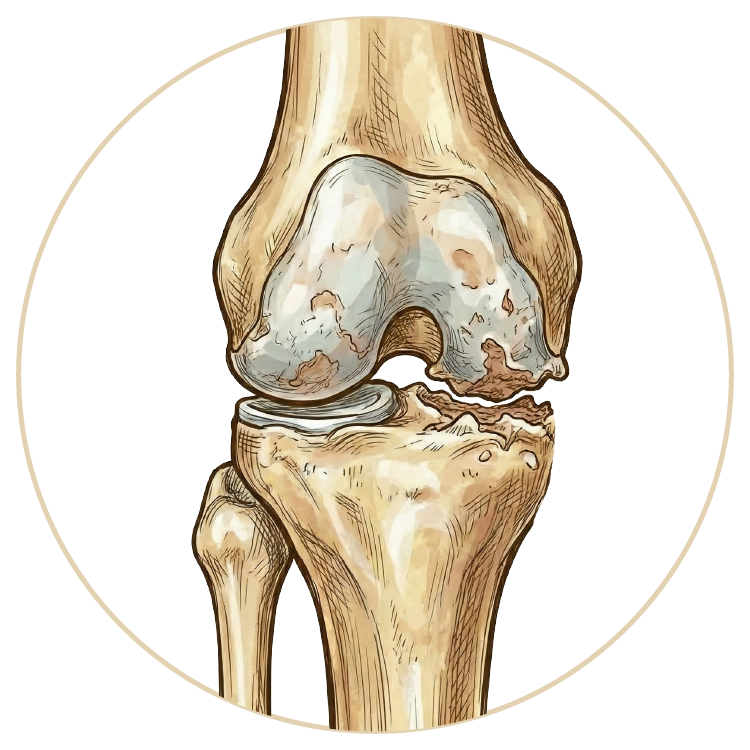

Diz Kireçlenme Tedavsi

Diz Protezi